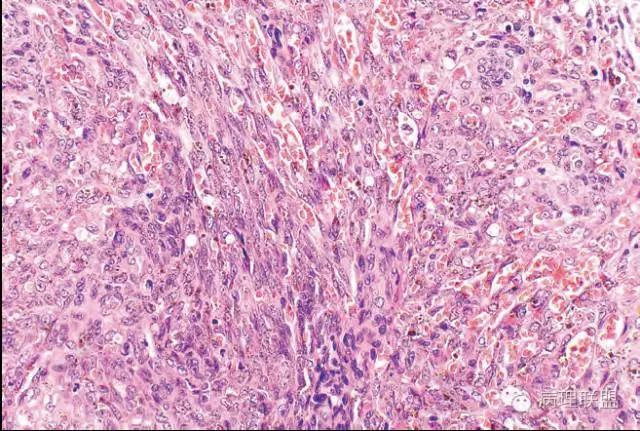

Kaposi型血管内皮瘤常有隐约小叶结构,梭形细胞束间有毛细血管,细胞核异型性和分裂活性一般不明显,常见梭形细胞束和圆形"肾小球样"实性细胞巢混合存在。

有些区域类似Kaposi肉瘤,如下图

而复合性血管内皮瘤则是由良性、中间性和恶性的成份组成,也是浸润性生长,常常侵犯皮下脂肪组织,此例细胞形态由梭形细胞、卵圆形细胞及上皮样细胞组成,形态可见良性区域、中间性区域及高分化血管肉瘤或上皮样血管肉瘤区域,因此,似乎复合性血管内皮瘤更妥。此类肿瘤可以发生于婴幼儿。当然与Kaposi型血管内皮瘤一样,同属中间性血管瘤,只是后者,若肿瘤体积大,可出现Kasabach-Merritt综合征。

这种形态若在老年人头面部就是血管肉瘤,而在婴幼儿就降级了。